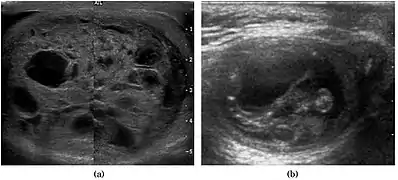

Teratoma Although teratoma is the second most common testicular tumor in children, it affects all age groups. Mature teratoma in children is often benign, but teratoma in adults, regardless of age, should be considered as malignant. Teratomas are composed of all three germ cell layers, i.e. endoderm, mesoderm and ectoderm. At ultrasound, teratomas generally form well-circumscribed complex masses. Echogenic foci representing calcification, cartilage, immature bone and fibrosis are commonly seen [Fig. 5]. Cysts are also a common feature and depending on the contents of the cysts i.e. serous, mucoid or keratinous fluid, it may present as anechoic or complex structure [Fig. 6].

Fig. 5. Teratoma. A plaque like calcification with acoustic shadow is seen in the testis.

Fig. 6. Mature cystic teratoma. (a) Composite Image. Mature cystic teratoma in a 29-year-old man. Longitudinal sonography image of the right testis shows a multilocular cystic mass. (b) Mature cystic teratoma in a 6-year-old boy. Longitudinal sonography of the right testis shows a cystic mass contains calcification with no obvious acoustic shadow.